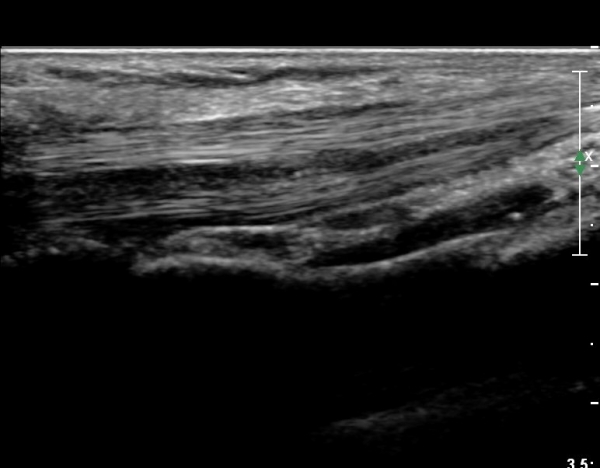

¼Õ¸ñ°ú ¼ö±Ù°ü±ÙÀ§ºÎ Ⱦ´Ü¸é°Ë»ç¿¡¼­  ÈûÁÙÀÇ ºñÈÄ¿Í ÈûÁÙ ÁÖÀ§ Ȱ¾×¸· ºñÈİ¡ °üÂûµÇ³ª

Á¤Áß½Å°æ ºÎÁ¾Àº °üÂûµÇÁö ¾Ê´Â´Ù(»çÁø 3, 4).